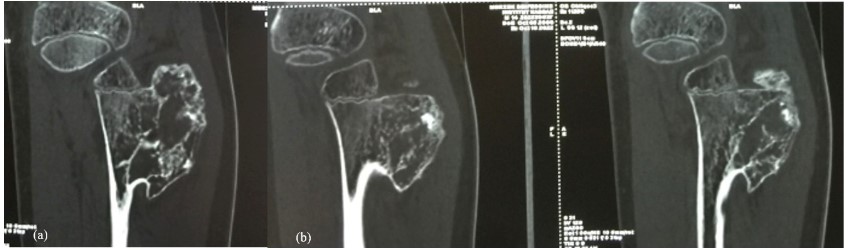

Knee x-ray showed a pedenculated tumor developing from the fibula neck (Figure 1a, 1b) increased in size compared with previous radiographs (Figure 2a, 2b). CT confirm findings with this “cauliflower like” exestosis developing from fibula neck with cartilage cap and with no invasion of the cortical bone (Figure 3).

Figure 3: (a,b): CT Scan showing voluminous “cauliflower like” pedenculated tumor arising from fibula neck with no sign of malignancy.